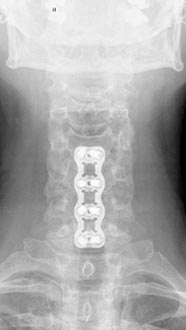

56 year old woman who presented with severe neck pain with numbness of both hands and balance problems due to severe cervical stenosis. Patient underwent C4 to C7 anterior cervical discectomy and fusion with complete resolution of her neurological symptoms.